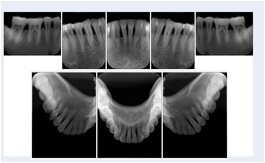

2. A patient requests cosmetic surgery to enhance their facial appearance. The case requires consultation between an orthodontist in New York and an oral surgeon in California. The cephalometric series of 2D projections constructed from the volumetric CT data that is used for the discussion is arranged by a Structured Display for transfer between the two practitioners.

Cephalometric Series Structured Display

Figure OO-2. Cephalometric Series Structured Display